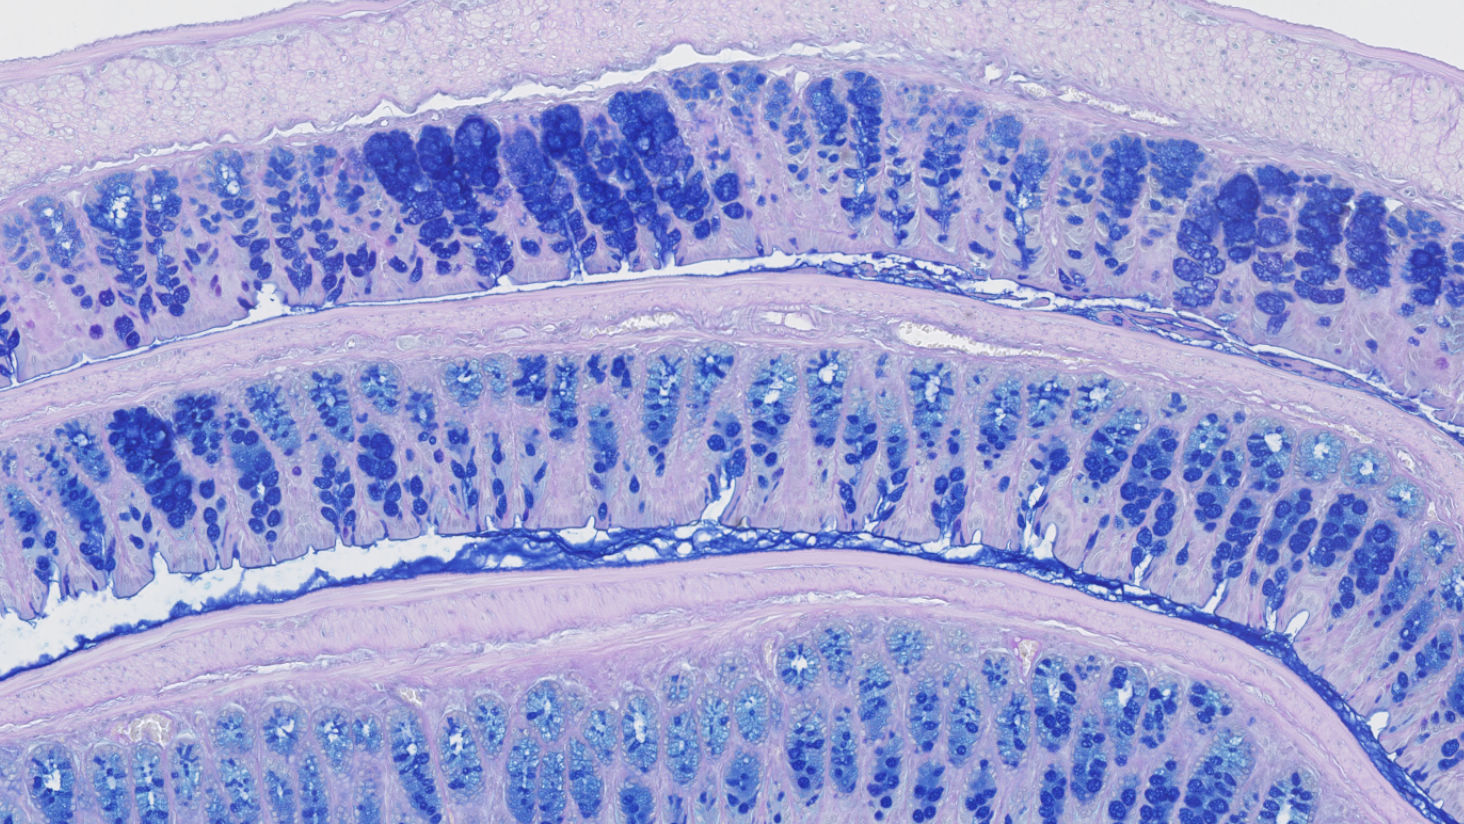

A typical screening cascade in an integrated inflammation program

While one of our clients, Oncodesign Precision Medicine (OPM), announced in February 2023 the initiation of Phase I of its RIPK2 inhibitor ODS-101 – a new therapeutic agent to treat Inflammatory Bowel Disease (IBD), we would like to share with you the screening cascade developed by Oncodesign Services that led to the identification of preclinical candidates.

We show the data of one of the selected preclinical candidate (ODS-002), which was prepared and tested via multiple step. This case study is a concrete example of our integrated service offering INPACT PoC Inflammation.

INPACT PoC Inflammation is an integrated preclinical pharmacology package to speed your selected drug candidate to the clinic. It combines the following capabilities to support your therapeutic discovery and innovation programs: